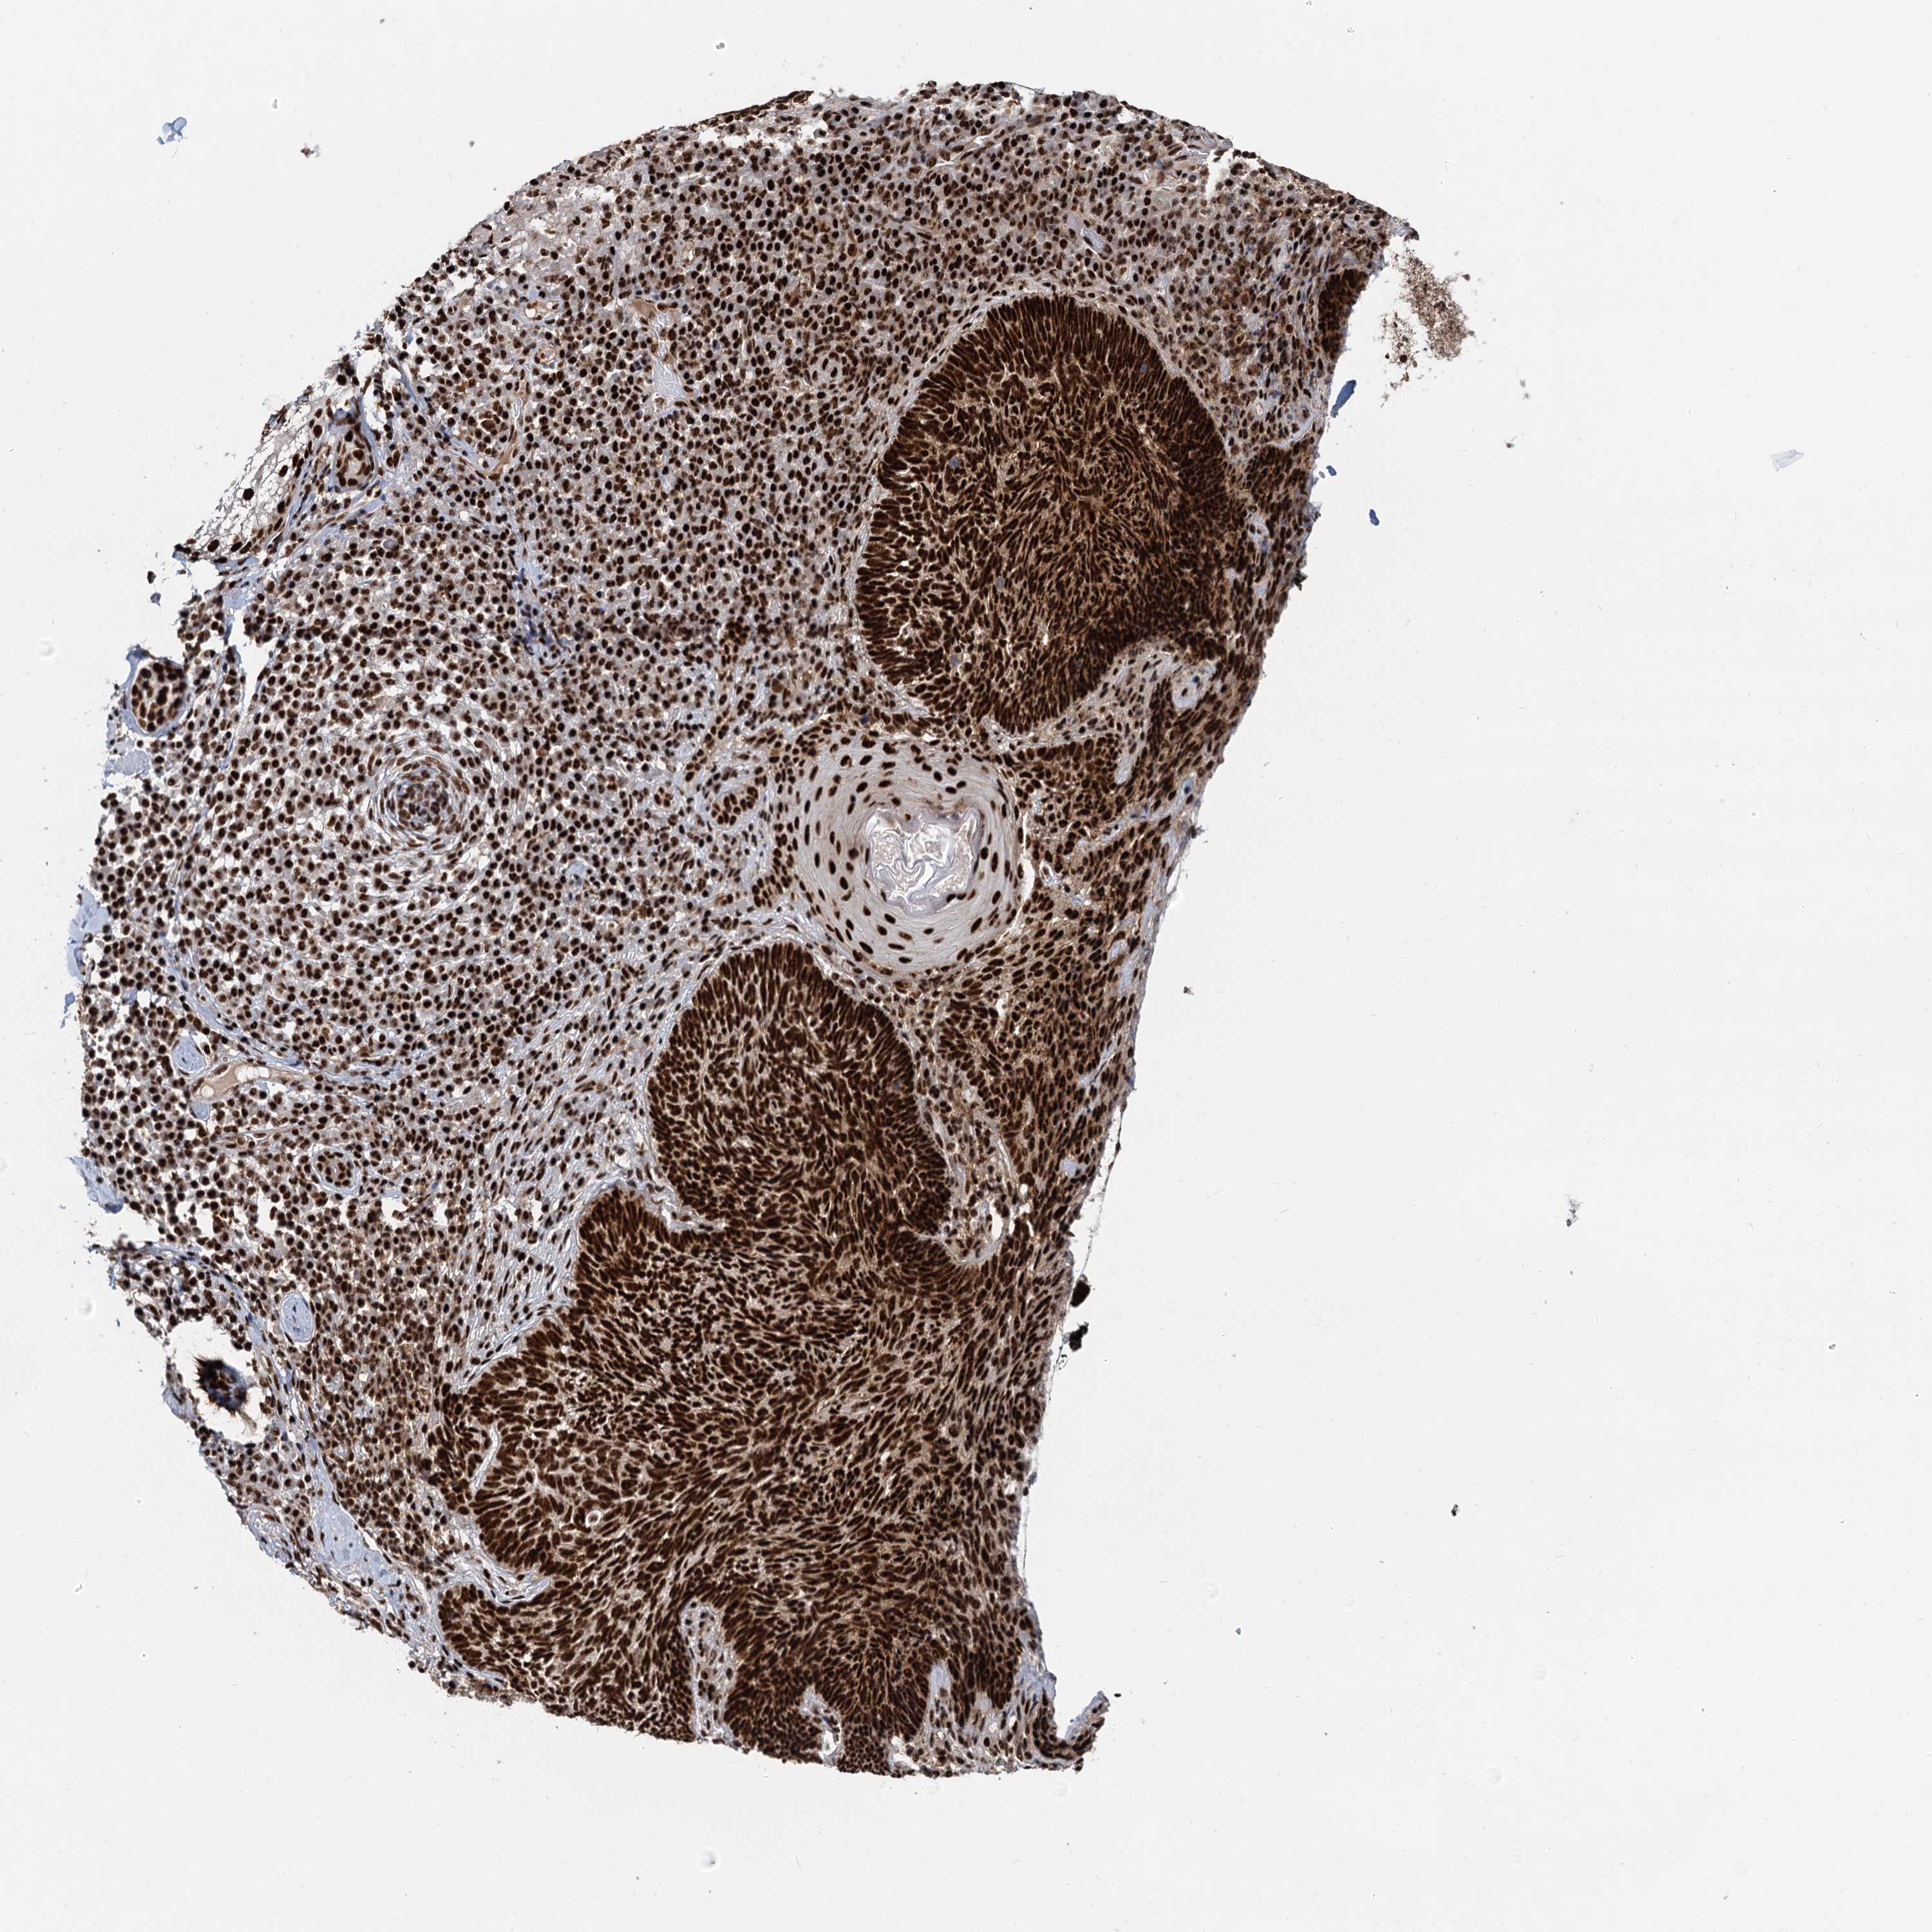

SKIN CANCER - Protein expressioni

A mouse-over function shows sample information and annotation data. Click on an image to view it in a full screen mode. Samples can be filtered based on level of antibody staining by selecting one or several of the following categories: high, medium, low and not detected. The assay and annotation is described here.

Antibody staining in the annotated cell types in the current human tissue is reported as not detected, low, medium, or high, based on conventional immunohistochemistry profiling in selected tissues. This score is based on the combination of the staining intensity and fraction of stained cells.

Each image is clickable and will lead to virtual microscopy that enables deeper exploration of all samples and also displays staining intensity scores, fraction scores and subcellular localization as well as patient and tissue information for each sample.

Antibody HPA040252

Staining

High

Medium

Low

Not detected

Intensity

Strong

Moderate

Weak

Negative

Quantity

>75%

75%-25%

<25%

None

Location

Nuclear

Cytoplasmic/membranous

Cytoplasmic/membranous,nuclear

Squamous cell carcinoma, metastatic, NOS